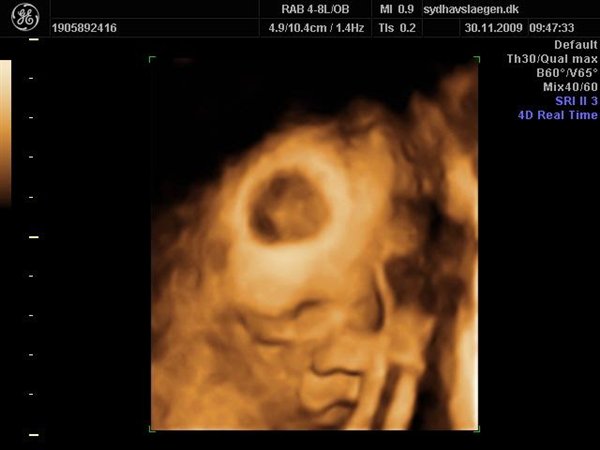

Vi skal give 1400 kr for 45 minutters total gennem scanning, hvor hun fortæller, undersøger babyen fra top til tå, laver vægtskøn også får vi billeder og dvd med hjem.... Og ja det er da mange penge, men min forlovede har haft en masse vikar timer den her mdr, også sagde han at han syntes vi skulle bruge de penge på noget vi normalt ikke ville have gjort. Han sagde egentlig at jeg kunne gå ud og shoppe for dem, men jeg har termin om ti uger, så gider ærlig talt ikke bruge penge på nyt graviditets tøj, så hellere det her som vi egentlig havde valgt fra pga prisen, men som vi begge to rigtig gerne vil....